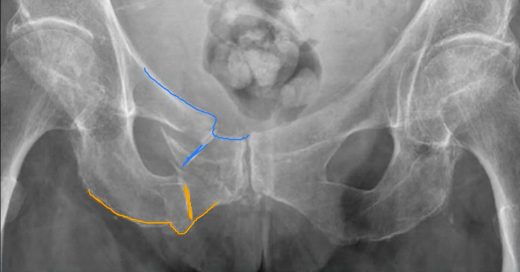

An 81 year old woman fell in her garden, and has pain in her right groin. Her right leg does not appear shortened or externally rotated. Her X-ray is shown.

What can you see?

What is meant by the ‘pubic ring’ and why is this important?

A 30 year old man was thrown from his motorbike at speed. His X-ray is shown.